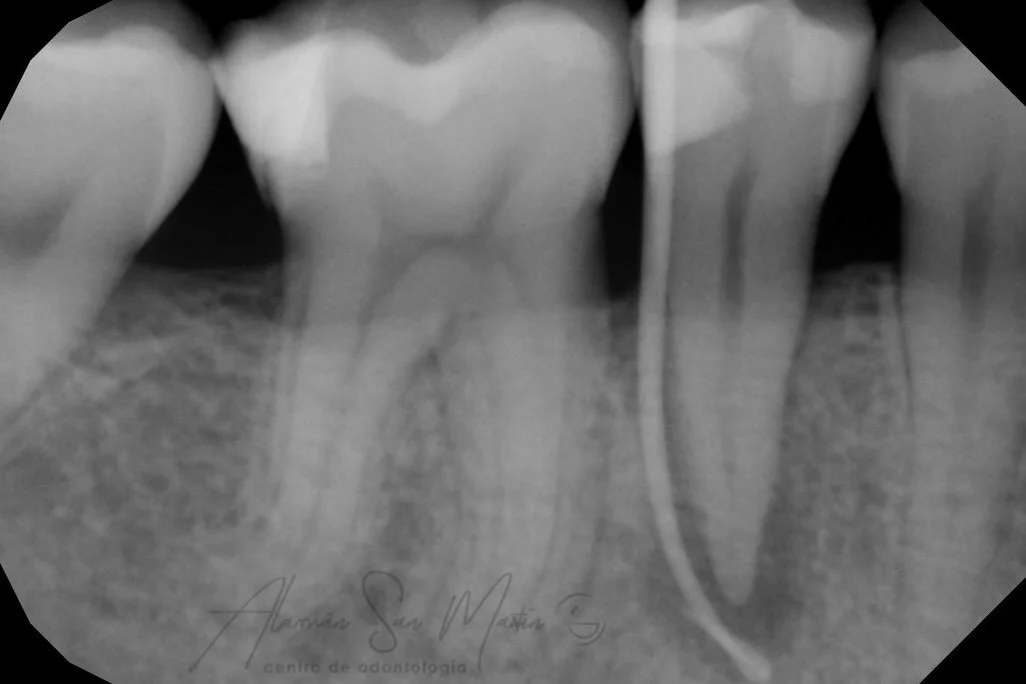

La Endodoncia consigue eliminar el nervio de los dientes con infección por caries o por algún traumatismo, y rellenarlo con material biocompatible, conservando el diente sin tener que extraerlo.

En nuestra clínica se realizan endodoncias por un Especialista En Endodoncia tratando desde casos sencillos a casos complejos de retratamientos o fracasos en endodoncias antiguas.

Utilizamos técnicas avanzadas de diagnóstico en endodoncia como la Radiovisiografía Digital, el Localizador de Ápice y Técnicas Rotatorias de instrumentación de los conductos radiculares, utilizando el microscopio en los pacientes que lo requieren.